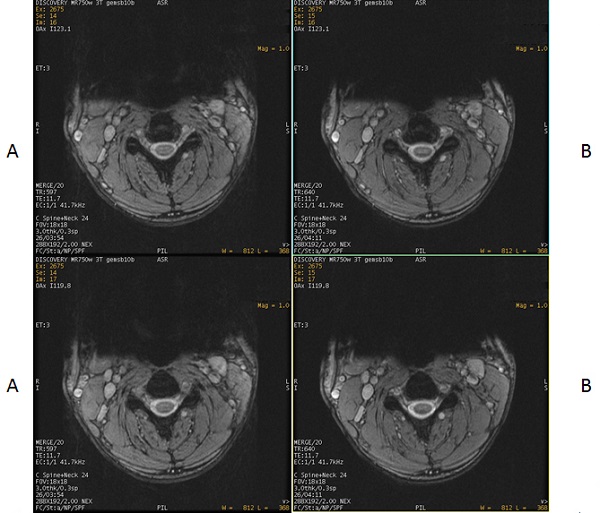

Figure 2. Exmaple of: Spatial SAT Level applied to 2D MERGE scan

Table 1. Image legend Number Description A Spatial SAT Level Light (0) applied anterior to the cervical spine. B Spatial SAT Level Medium (1) applied anterior to the cervical spine.